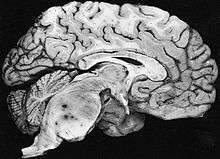

Fibrillary astrocytomas arise from neoplastic astrocytes, a type of glial cell found in the central nervous system. They may occur anywhere in the brain, or even in the spinal cord,[1] but are most commonly found in the cerebral hemispheres. As the alternative name of "diffuse astrocytoma" implies, the outline of the tumour is not clearly visible in scans, because the borders of the neoplasm tend to send out tiny microscopic fibrillary tentacles that spread into the surrounding brain tissue. These tentacles intermingle with healthy brain cells, making complete surgical removal difficult. However, they are low grade tumors, with a slow rate of growth, so that patients commonly survive longer than those with otherwise similar types of brain tumour, such as glioblastoma multiforme.[1]